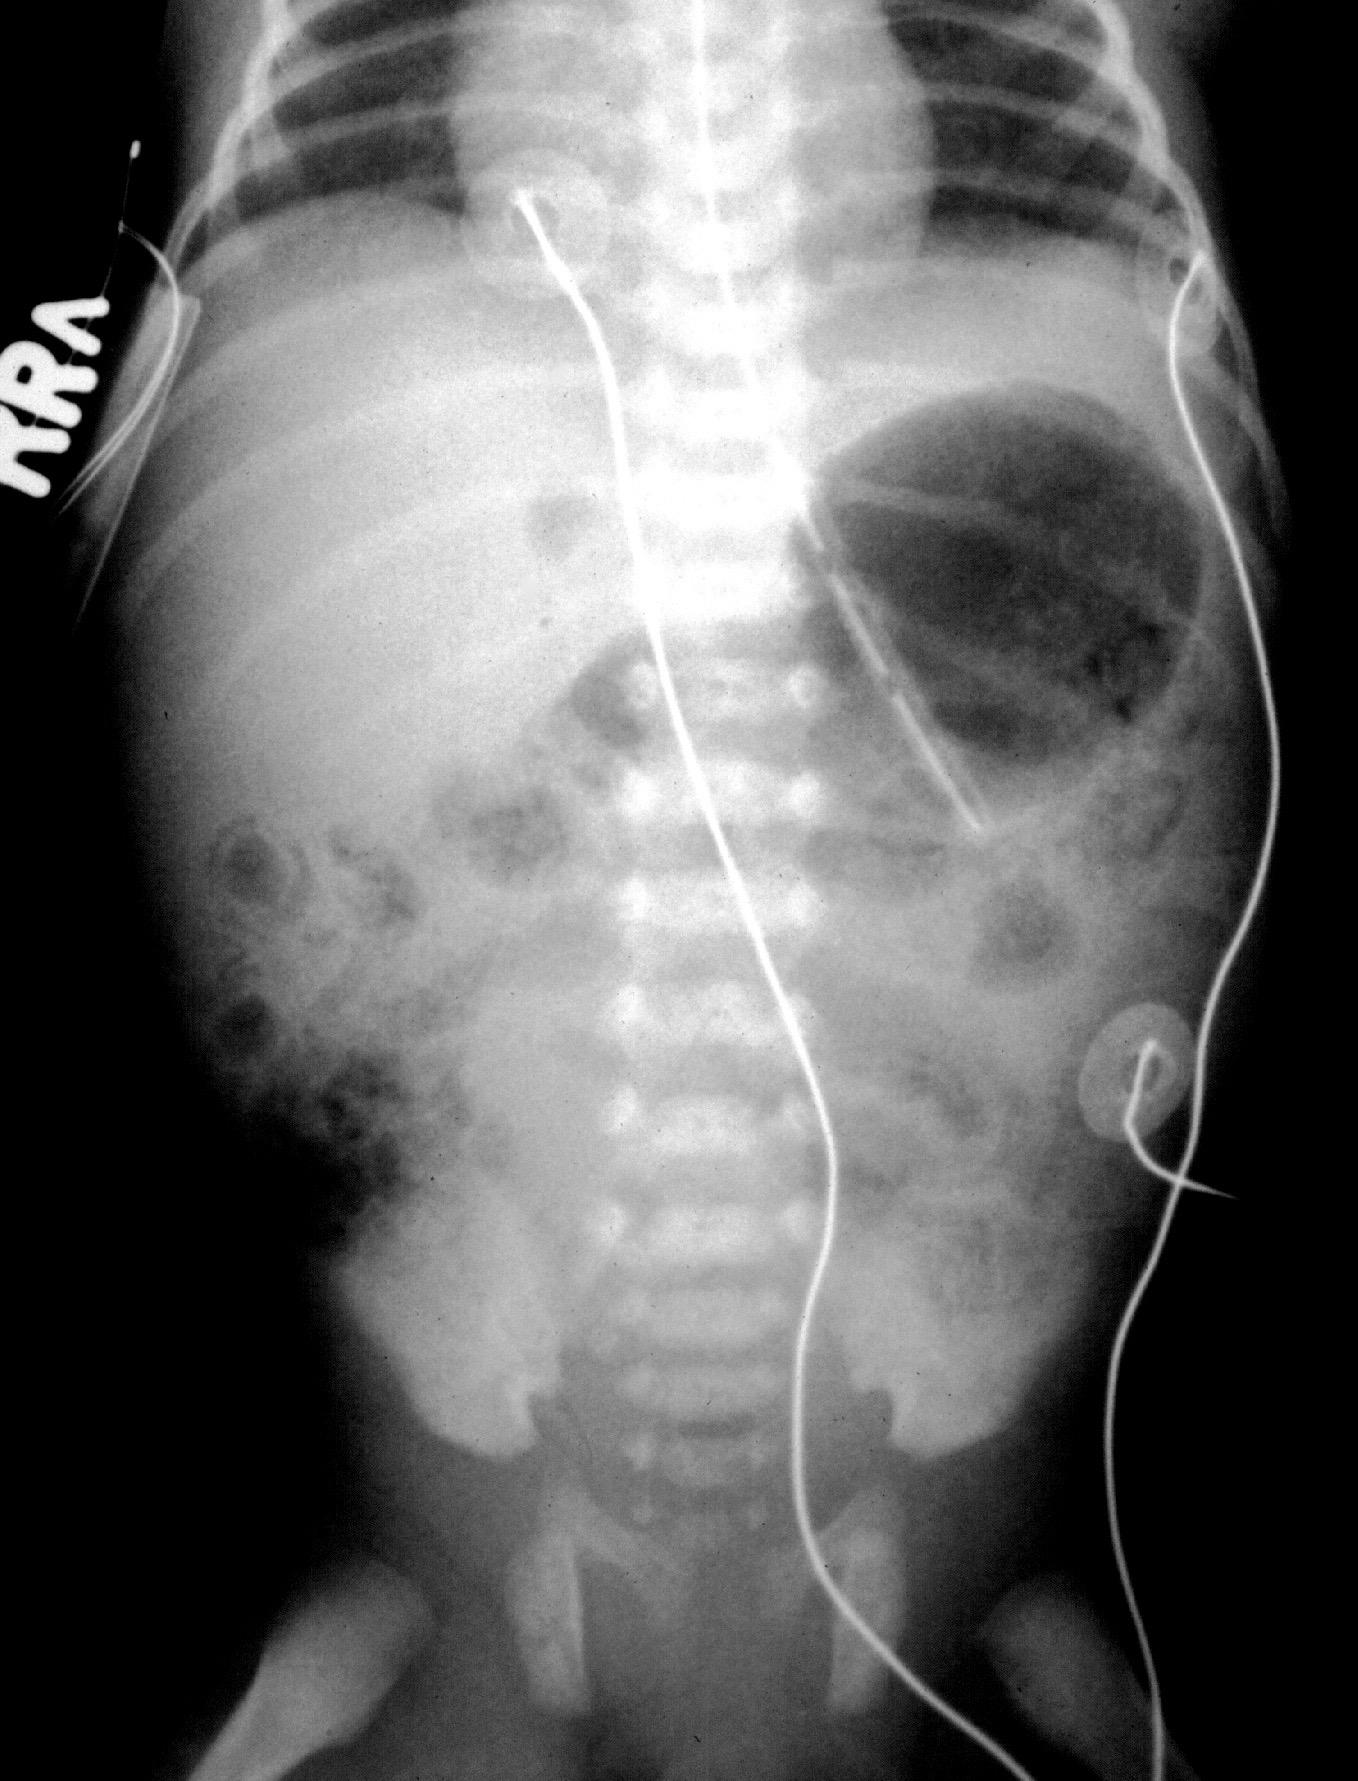

Colitis In Premature Babies. Such bowel wall destruction can lead to perforation of the intestine and. This can lead to a perforation (hole) developing, which allows the contents of the intestine to leak into the abdomen (tummy). It occurs in nearly 10% of premature infants. Moreover, in babies with nec, a switch that acts like a brake is turned on inside their intestinal cells, abruptly halting the enterocytes� movement.

It is a devastating gastrointestinal disease that is associated with severe sepsis, intestinal perforation, and significant morbidity and mortality 1. It is a serious condition that might generate long term effects in babies, and sometimes even death. Such bowel wall destruction can lead to perforation of the intestine and. Intussusception is a rare entity in neonates. Pcmv is usually asymptomatic in term infants, but can cause symptomatic disease in preterm (gestational age <32 weeks) and very low birth weight (<1500. The wall of the intestine is invaded by bacteria, which cause local infection and inflammation that can ultimately destroy the wall of the bowel (intestine).

A baby with allergic colitis may be extremely fussy, difficult to console, and develop flecks or streaks of blood in the stool. Necrotizing enterocolitis (nec) is a devastating disease that affects mostly the intestine of premature infants. Necrotizing enterocolitis, or nec, is a serious disease that affects the intestines of premature infants. In premature infants, nec is a common gastrointestinal illness. It happens when tissue in the small or large intestine is injured or inflamed. Some infants also have diarrhea and vomiting, and some may show.

Nec may lead to serious health problems and complications, including: This can lead to a perforation (hole) developing, which allows the contents of the intestine to leak into the abdomen (tummy). Ultrasound can help to establish early diagnosis in neonate. Such bowel wall destruction can lead to perforation of the intestine and. Necrotizing enterocolitis is a serious gastrointestinal problem that mostly affects premature babies.

This can lead to death of intestinal tissue and, in some cases, a hole (perforation) in the intestinal wall. Necrotizing enterocolitis (nec) is a serious intestinal illness in babies. The wall of the intestine is invaded by bacteria, which cause local infection and inflammation that can ultimately destroy the wall of the bowel (intestine). This can cause a very dangerous infection.this page explains about necrotising enterocolitis. Necrotising enterocolitis (nec) is a serious illness in which tissues in the intestine (gut) become inflamed and start to die.

Colitis means inflammation of the colon (lower part of the intestine) although nec may develop in any newborn, most cases occur in premature babies and in up to 5 percent of babies in newborn intensive care units. Ultrasound can help to establish early diagnosis in neonate. How common is necrotizing enterocolitis? Necrotizing enterocolitis (nec) is a devastating disease that affects mostly the intestine of premature infants. Colitis means inflammation of the colon (lower part of the intestine) although nec may develop in any newborn, most cases occur in premature babies and in up to 5 percent of babies in newborn intensive care units.

Pcmv refers to postnatal acquisition of cmv rather than postnatal manifestations of antenatal or perinatal acquired cmv. The wall of the intestine is invaded by bacteria, which cause local infection and inflammation that can ultimately destroy the wall of the bowel (intestine). Necrotizing enterocolitis (nec) is a serious intestinal illness in babies. Ultrasound can help to establish early diagnosis in neonate. Necrotizing = damage and death of cells entero = referring to the intestine colitis = inflammation of the lower part of the intestines (colon).

It occurs in nearly 10% of premature infants. Necrotizing = damage and death of cells entero = referring to the intestine colitis = inflammation of the lower part of the intestines (colon). Necrotizing enterocolitis (nec) is a very serious illness that most commonly occurs in the intestines of preterm babies. Nec mostly affects premature babies. Nec may lead to serious health problems and complications, including:

Necrotizing enterocolitis (nec) is a condition characterized by variable injury or damage to the intestinal tract, causing death of intestinal tissue. Though the published cases have appeared under diverse titles including neonatal appendicitis (4, 18, 22), peritonitis (12), colitis (21), ileitis (1), pneumatosis intestinalis (20), or portal vein gas in infants (10. 1) significantly increased risk of preterm birth when women give birth. Necrotizing enterocolitis (nec) is a condition characterized by variable injury or damage to the intestinal tract, causing death of intestinal tissue. Necrotizing enterocolitis (nec) is a serious intestinal illness in babies.

Necrotizing enterocolitis (nec) is a condition characterized by variable injury or damage to the intestinal tract, causing death of intestinal tissue. Such bowel wall destruction can lead to perforation of the intestine and. Postnatal cytomegalovirus (pcmv) infection is a common viral infection typically occurring within the first months of life. This disease, which can often require surgery to remove damaged sections of intestine, often develops two to three weeks after birth but can occur much later. Necrotizing enterocolitis (nec) is a serious intestinal illness in babies.